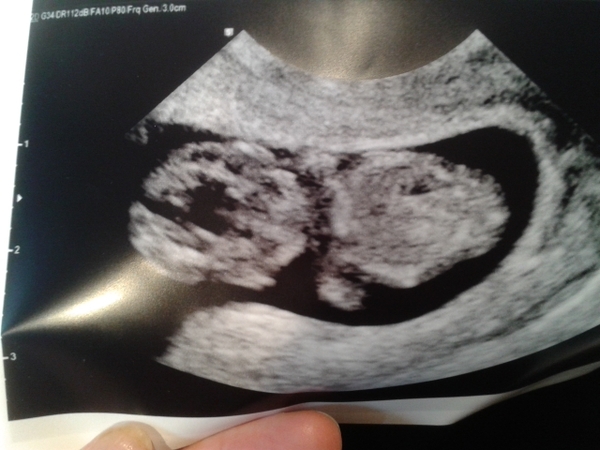

Here is babydos!